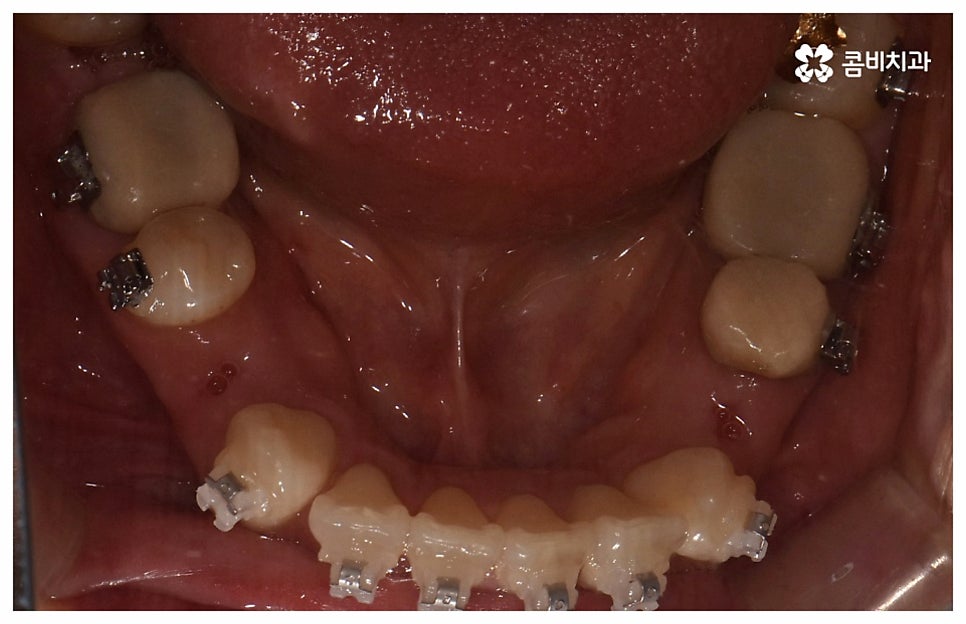

검진 후 부분 교정이 가능하지 않은 케이스라고 해도 요즘은 심미적인 교정 장치가 많이 나와 있으며 장치 자체로 인해 결과에 미치는 영향이 크지 않기 때문에 자신의 상황에 맞는 장치를 직접 선택할 수 있으니 의료진과 충분히 상담을 해 보시면 도움 받아 보실 수 있을 거예요. 특히 치아 색상의 브라켓을 이용한 세라믹 장치들이 심미성이 뛰어난데, 그 중에서도 자가결찰방식을 이용한 클리피씨 교정 장치를 이용하면 눈에 크게 띄지 않을 뿐 아니라 보다 적은 힘으로 부드럽고 지속적인 치아 이동을 가능하게 하기 때문에 통증도 줄이고 전체 교정 기간 역시 단축시킬 수 있다는 장점이 있으니 이에 대해서도 자세하게 알아보시길 바라고 있습니다.

위 사진은 환자분의 동의를 받아 이해를 돕기 위한

사진이며, 실제 치료 결과는 다를 수 있습니다.